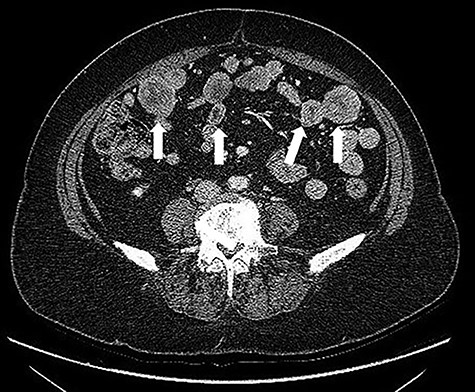

A 68-years-old woman (body mass index 35.6) was admitted with recent onset sideropenic anemia and not heart-related angina pectoris. At physical examination, a slightly mobile mass in the left iliac fossa was palpable. Carcinoembryonic antigen, carbohydrate antigen 19.9 (CA 19.9) carcinoma antigen 125 (CA 125) were normal. Upper and lower GI endoscopy were negative for any lesion. The patient was submitted for computed tomography (CT) scan, showing multiple solid density processes with colliquation areas in the abdominal cavity (Fig. 1). The greatest mass (8.0 × 5.6 cm) was located in the pelvis in close contact with the uterine fundus and the small bowel (Fig. 2). Cranially to this process, at least 20 other tumors with a diameter between 0.8 and 3.8 cm could be appreciated.

CT scan: multiple solid density processes with colliquation areas within them (white arrows) in the abdominal cavity.